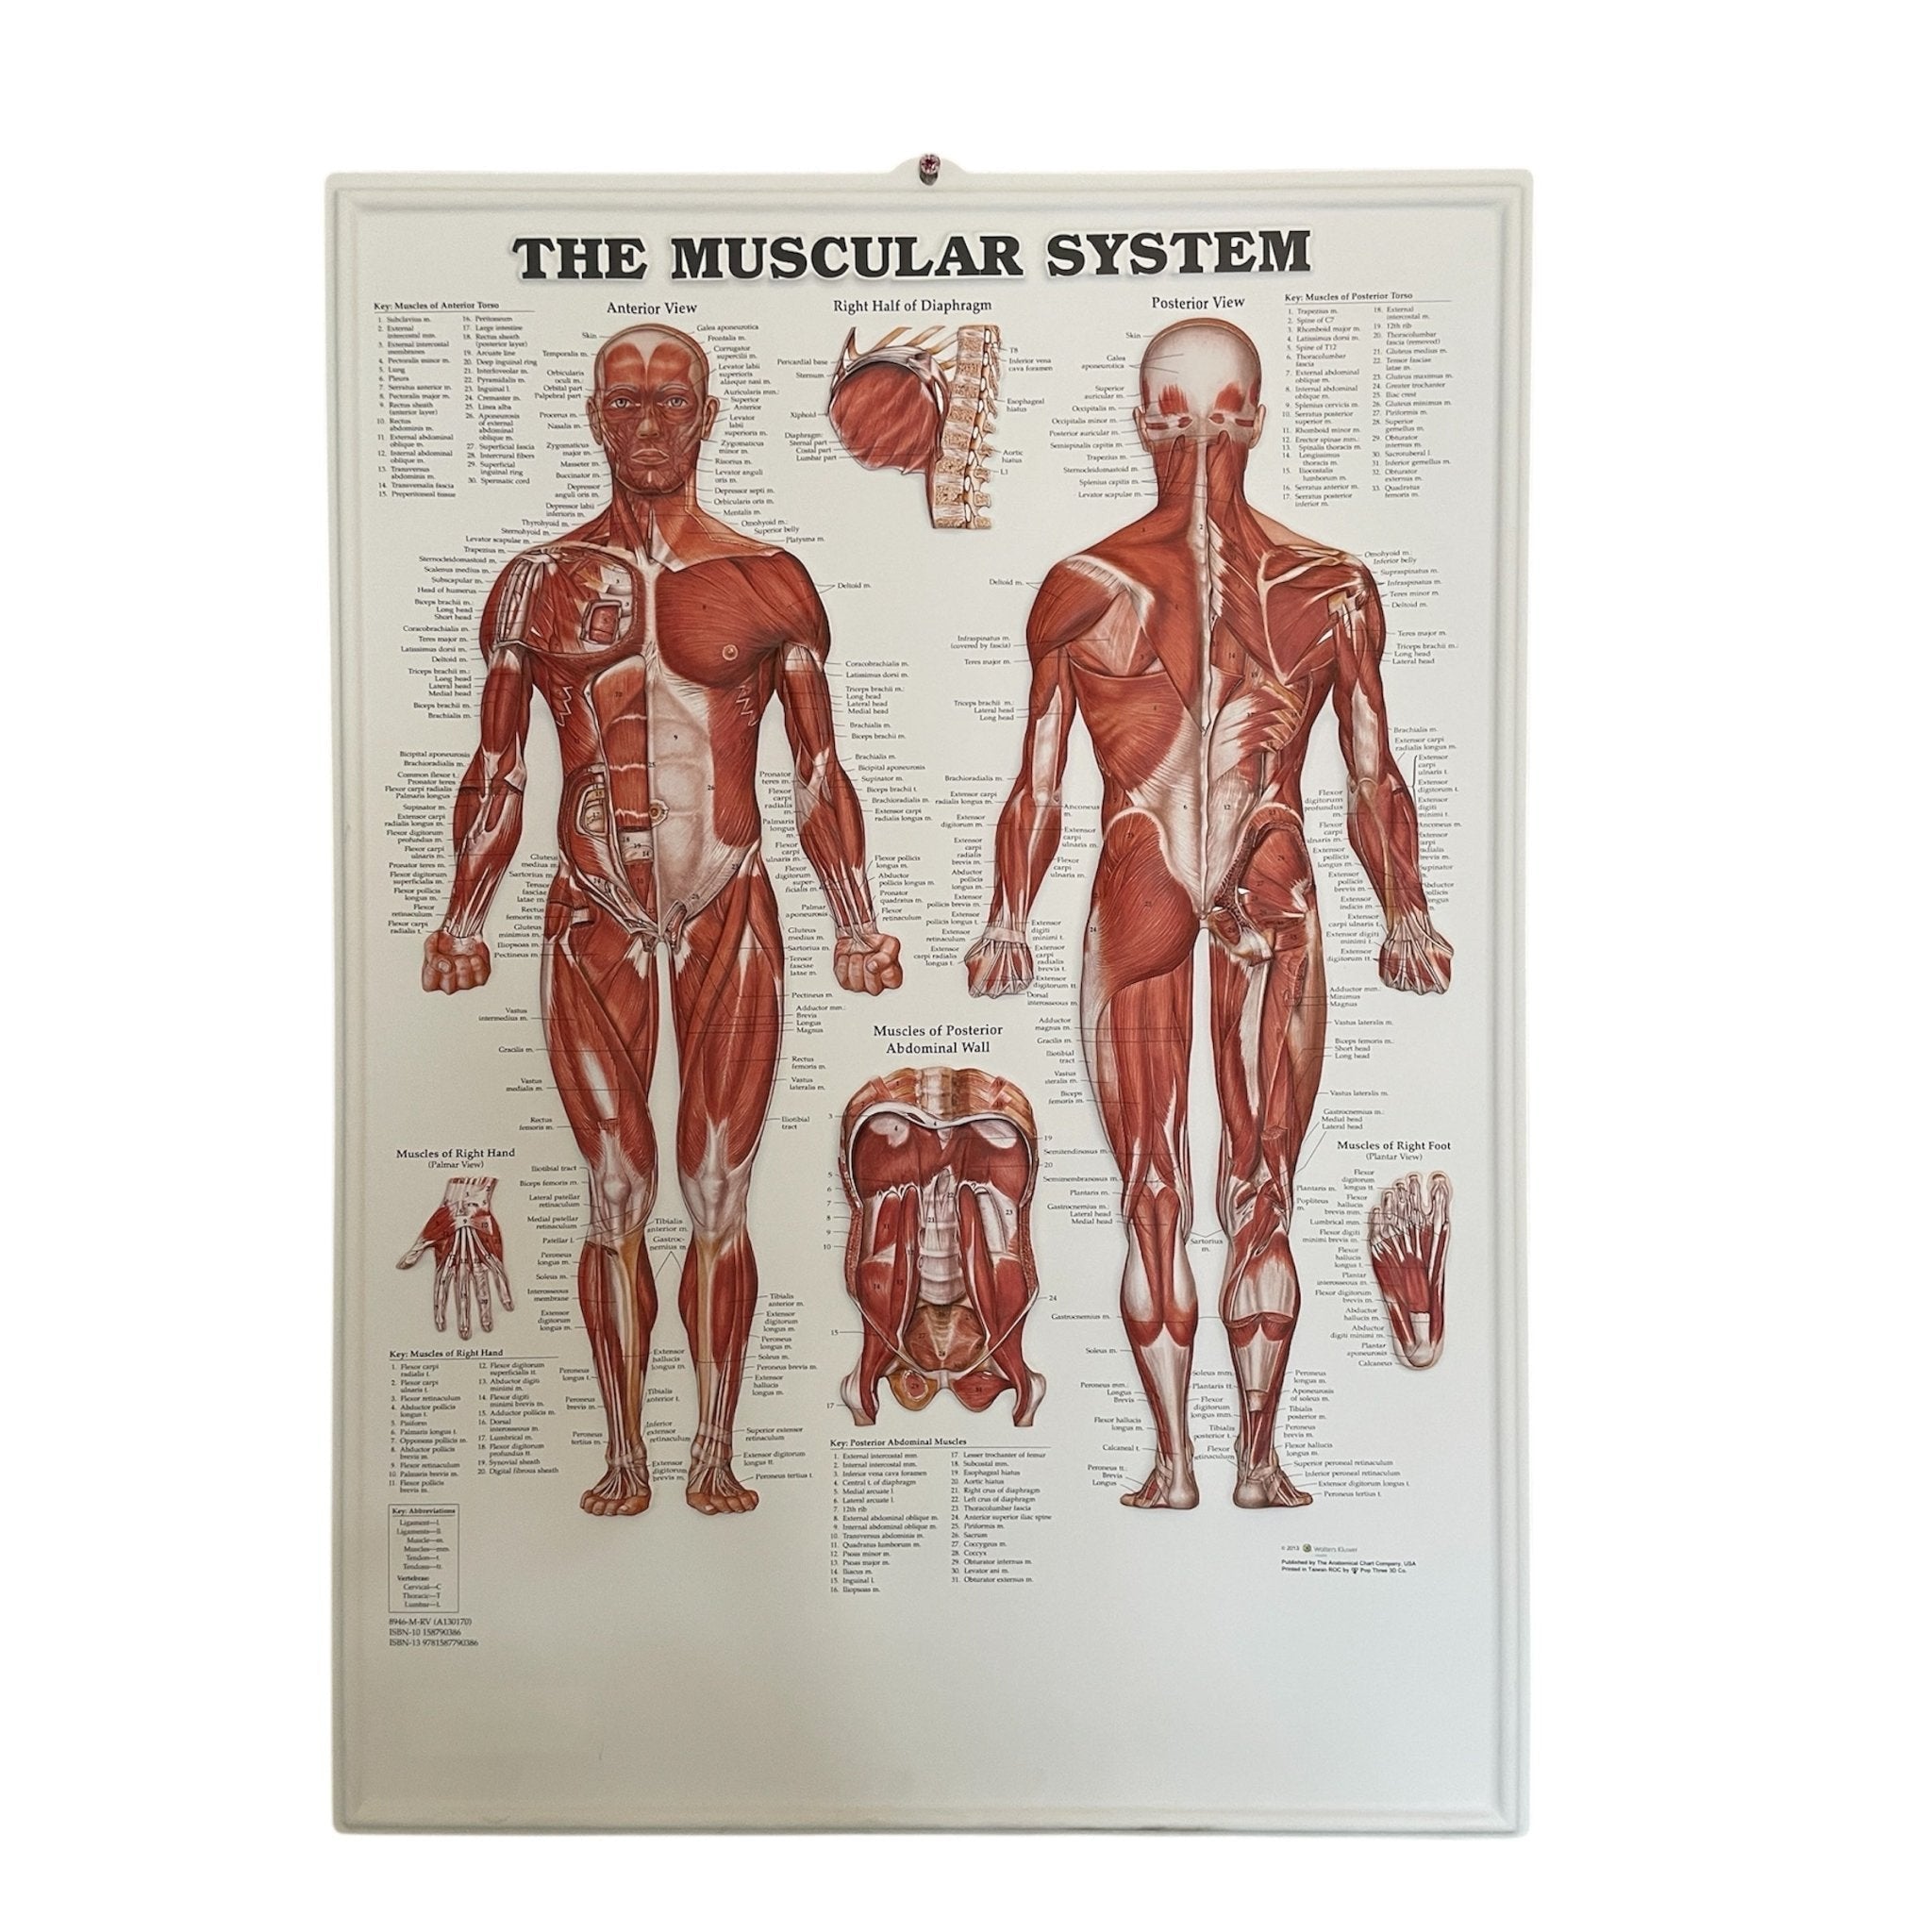

Muscle posters

Muscles provide movement to the musculoskeletal system, and their origins, insertions and lodges are clinically important for every healthcare professional. That is why we at eAnatomi have both developed and designed our own anatomy posters, which provide the ultimate overview of all the muscles of the body. On this page you can find both our own posters and posters from other manufacturers. We offer posters in several different languages such as pure Latin, Danish, English and Swedish, etc.